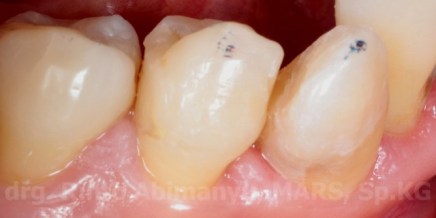

Keadaan awal gigi 43

Gigi 43 mengalami karies dan sudah terlihat perforasi ke kamar pulpa, perkusi negatif, dan respon dingin menunjukkan positif. Kemudian dari ronsen terlihat seperti ini..